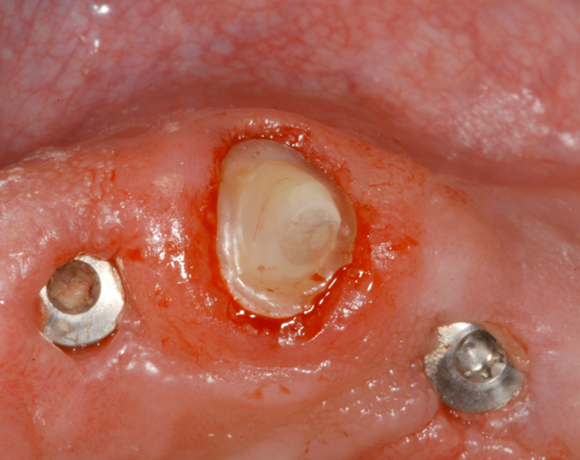

Im nachfolgenden Patientenfall wird ein Zahn mit einem Stift soweit aufgebaut, dass es möglich wird ihn wieder mit einer Krone zu versorgen.